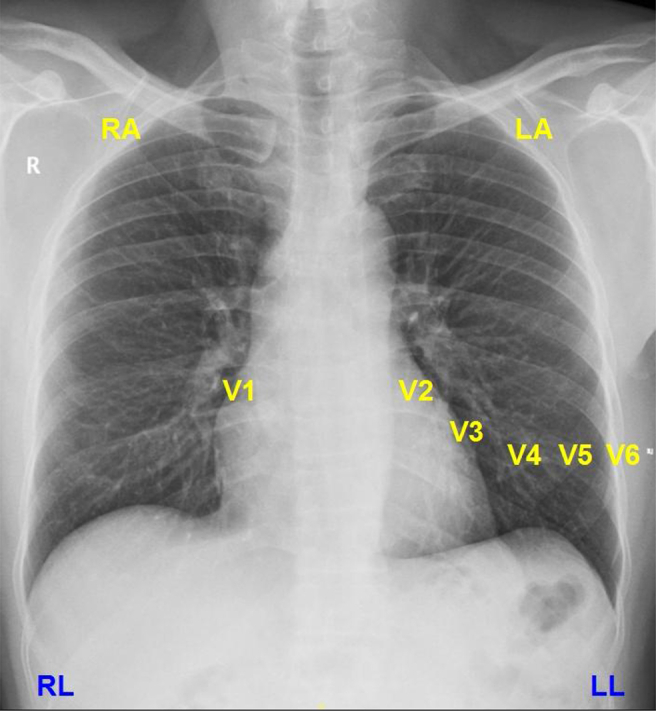

要做一份合格的心电图,首先应熟悉正常导联的位置,肢体导联应注意左右、上下的区别,而胸导联应熟记每一个导联的位置,包括18导联心电图。

表1 胸导联位置

图1 常用导联位置示意图